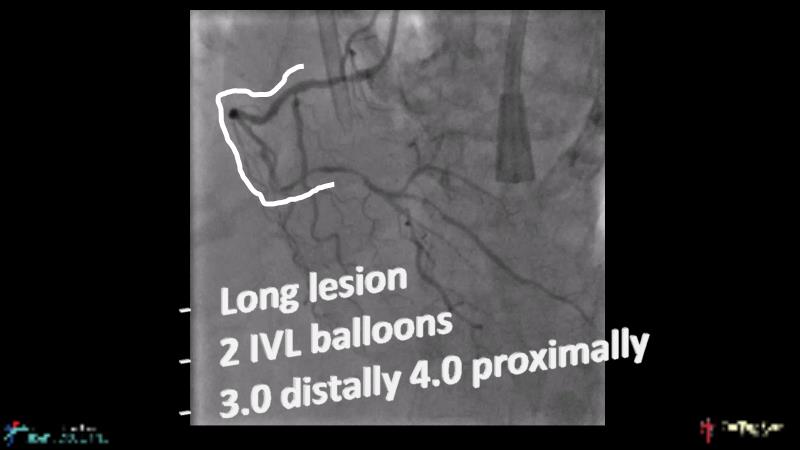

With this session, keep up to date on the evidence, trials and outcome data for intravascular lithotripsy in severely calcified lesions. Learn how to use this technique in real-world patients and understand its role in the treatment algorithm for severely calcified coronary lesions.

- To know the evidence, trials and outcome data for intravascular lithotripsy in severely calcified lesions

- To learn how to use intravascular lithotripsy in real-world patients with severely calcified coronary lesions

- To understand the appropriate role of intravascular lithotripsy in the treatment algorithm for severely calcified lesions